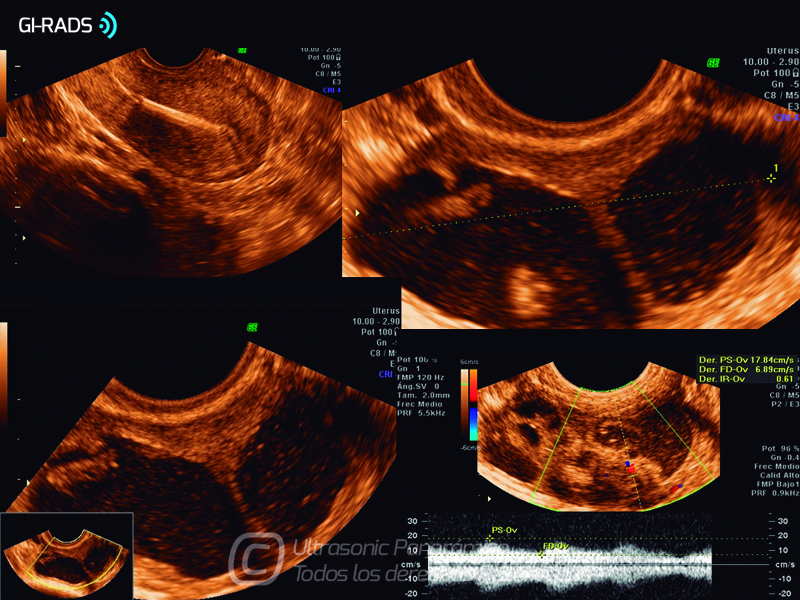

Patologías Benignas – Abceso Tubo Ovárico

• Patologías Benignas – Abceso Tubo Ovárico